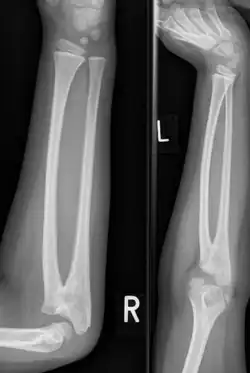

Plain radiograph showing fusion of the radius and ulna

Congenital radioulnar synostosis in a 7-year-old boy

Radioulnar synostosis is a rare condition where there is an abnormal connection (synostosis) between the radius and ulna bones of the forearm.[1] This can be present at birth (congenital), when it is a result of a failure of the bones to form separately, or following an injury (post-traumatic).[2]